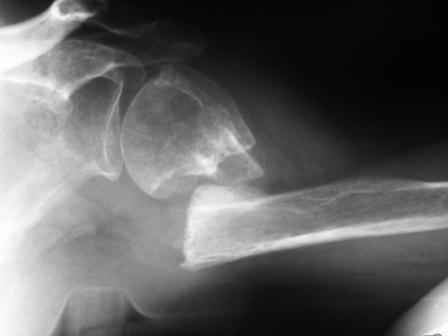

Дорогие друзья, наверное, можно обойтись здесь и без chronOS. Ведь аутокость обладает лучшими остеокондуктивными, остеоиндуктивными и остеогенными свойствами. Но мне принципиально нравится то, как ведёт себя chronOS. И, если это возможно, я всегда (или практически всегда) стараюсь потенциировать остеоиндуктивные свойства аутокости ещё и этим В3кальций фосфатом в случаях лечения ложных суставов. В прикреплённом ПДФ файле - 2 клинических случая. В первом ложный сустав локтевой кости после своеобразного остеосинтеза пластиной у молодого человека 30 лет. Выполнена декортикация, под декортиканты уложены гранулы chronOS. Остеосинтез. Активность немедленная, результат через год. По моему, В3кальций фосфат неплохо заместился костью? Второй случай посложнее и соответствует заданному Леонидом вопросу. Леонид, дабы не возвращаться снова, если Вам итересно моё мнение, то у Вашей пациентки я бы постарался выполнить нечто подобное. Немолодая (83 года) интеллигентная женщина обратилась в нашу клинику полтора года назад с несросшимся переломом и мигрировавшим фиксатором проксимального плеча. Там, где выполнили первичную фиксацию (в Москве, ясен пень) посоветовали *носить руку в кармане*, что для нормального человека, согласитесь, не всегда приемлемо. Да, здесь я выбрал PHILOS. Кстати, пишется именно так, поскольку это аббревиатура от the Proximal Humerus Internal LOcking System. Трансплантат из гребня подвздошной кости и немного гранул chronOS. А вот как и зачем здесь размещать инъекционную форму chronOS - полностью согласен с Александром Ч. - не знаю. Через год - хорошее заживление перелома при очень неплохой функции и отсутсвии боли. Имплантат решили не удалять. С уважением, Андрей Волна